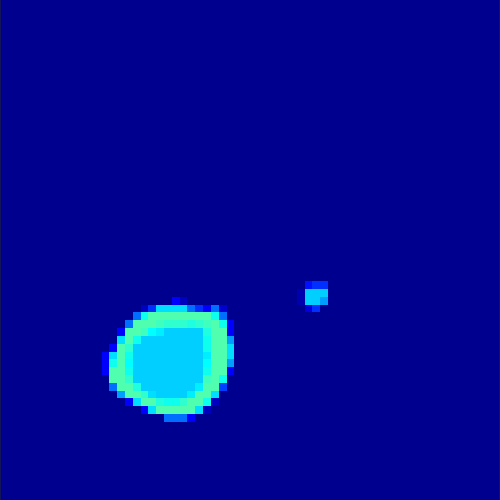

5.2 Monte Carlo Simulation

In order to test the behaviour of the proposed method in a more realistic, random-based test case, we performed a Monte Carlo simulation for dynamic SPECT imaging. First, we created a simple image phantom consisting of an outer and two inner circles which represents the structure of the region of interest (see figure 8(a)). Within those regions we assumed concentration curves over a time period of 90 time steps as displayed in figure 8(b). Based on the tracer intensity in an image frame at each time step, we created a variable number of random decay events (where the number is proportional to the average concentration in one pixel in the whole image frame per time step) with a probability proportional to the concentration in every subregion. They are detected by a virtual double head gamma camera rotating around the patient by 46 degrees per time step, which consists of 374 detector bins. Every simulated decay event is projected onto the scanner and counted by the corresponding detector bin.

In two different tests we fixed the number of events counted by the detector equal to (resp. ) times the average concentration in one pixel. The resulting sinogram images of the accumulated counts in each bin are shown in figure 9.

Based on the sinogram data we applied the proposed algorithm in order to reconstruct the original image sequence. The results for both test cases are shown in figure 10.

As one can see, the method is able to reconstruct the regions properly, even in case of a low count number. Within a number of iterations (average of 100 outer and 10000 inner iterations), the algorithm presents a reasonable reconstruction of the region of interest and the corresponding regional tracer concentration curves. Here, the parameters were not optimized as in the case of the synthesized data sets in the previous section, but kept fixed as , and . With futher optimized parameter values one could possibly provide even better results.